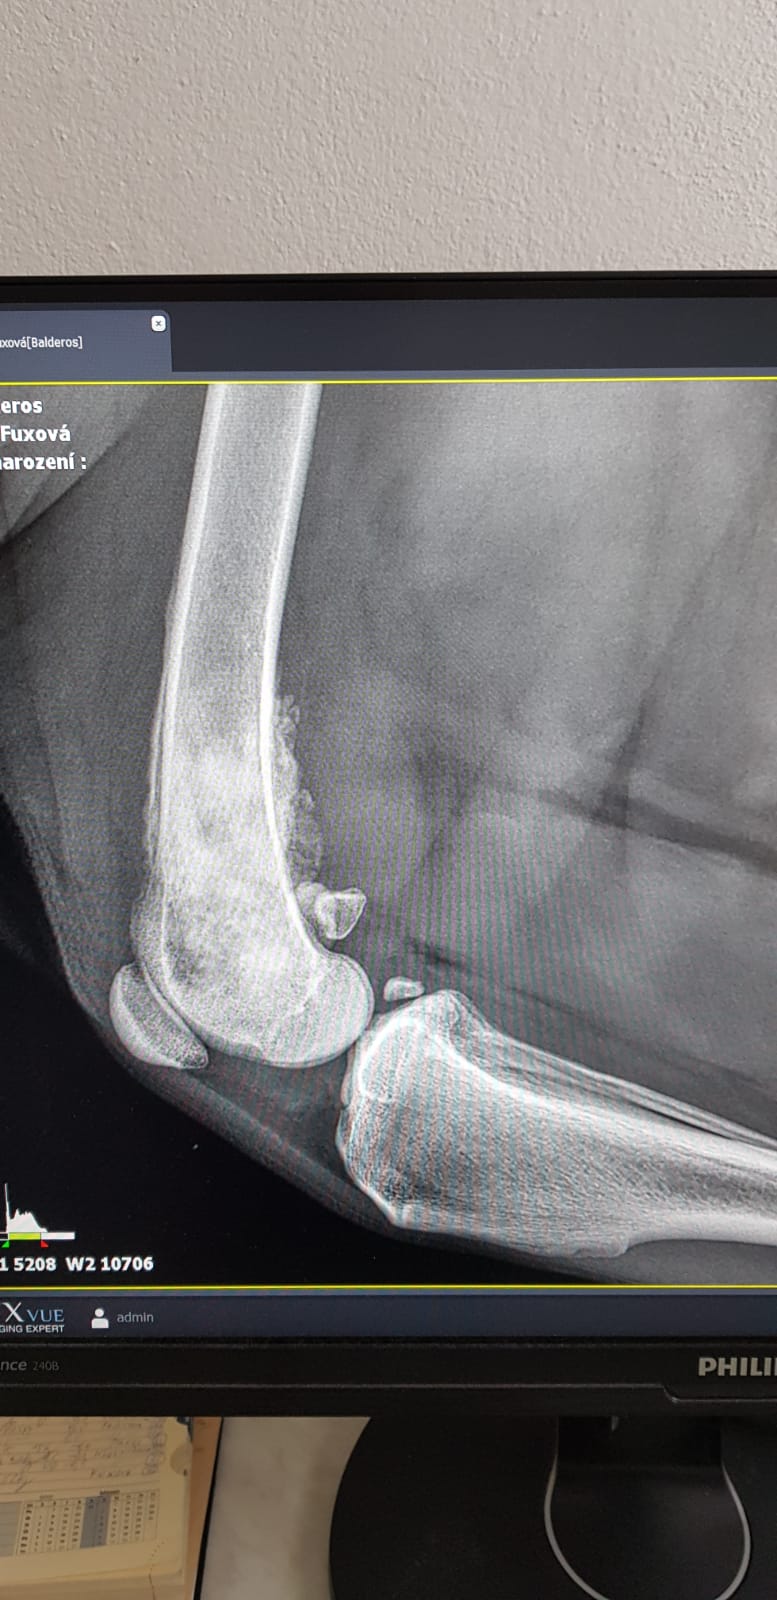

Dobrý den, moc prosím o radu. Náš 6lety leonberger začal kulhat na pravou zadní nožičky, mysleli jsme vazy. Dnes jsme s nim byli na RTG a jsme úplně v šoku, prý rakovina kostí a nedá se to operovat. Chtěla bych znát více názorů, posílám foto, co můžeme udělat, jak mu zpříjemnit život a jak rychle se bude chudák zhoršovat? Moc děkuji za odpověď, LF.

Dobrý den. Tohle je spíše dotaz pro onkologa, nebo ortopéda ., objednejte se :/ MVDr Musil, MVDr Vlach- Vetpark Brandýs,. Veterinární nemocnice AA-Vet , zahradní Město- najít na internetu /. Držím palce. S pozdravem MVDr Jančík.